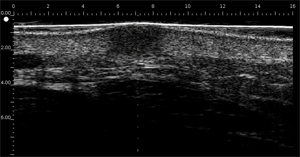

Acné

Le derme est échogène. Les échos proviennent du réseau de fibres collagènes et de fibres élastiques. Par rapport au derme, les lésions (tumeurs, kystes, angiomes…) apparaissent comme des zones hypoéchogènes.